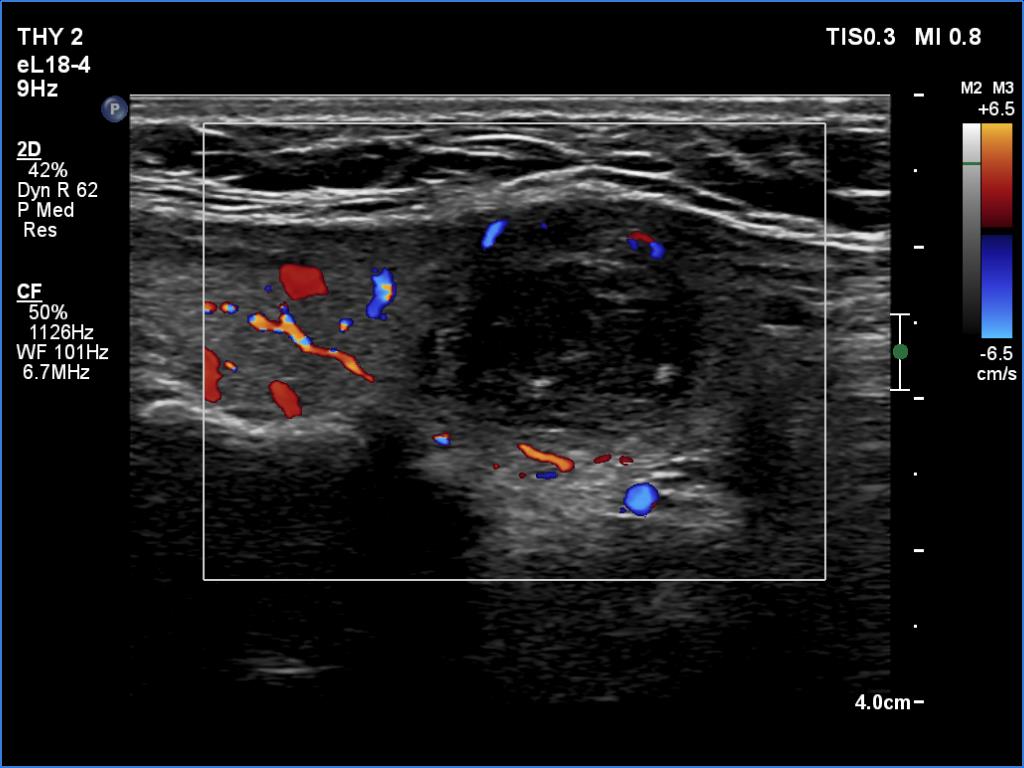

Ultrasonography revealed an echonormal thyroid. There was dominantly moderately hypoechoic nodule in the right lobe. Some parts of the lesion were deeply hypoechoic, and a few small cystic chambers were also within. The nodule presented with irregular shape and borders and had intranodular echogenic figures, primarily granules.

It is ambiguous how to interpret the echogenic figures. Although the presence of irregular shape and borders increases the likelihood that the echogenic granules are indeed microcalcifications, comet-tail artifacts must be also considered.